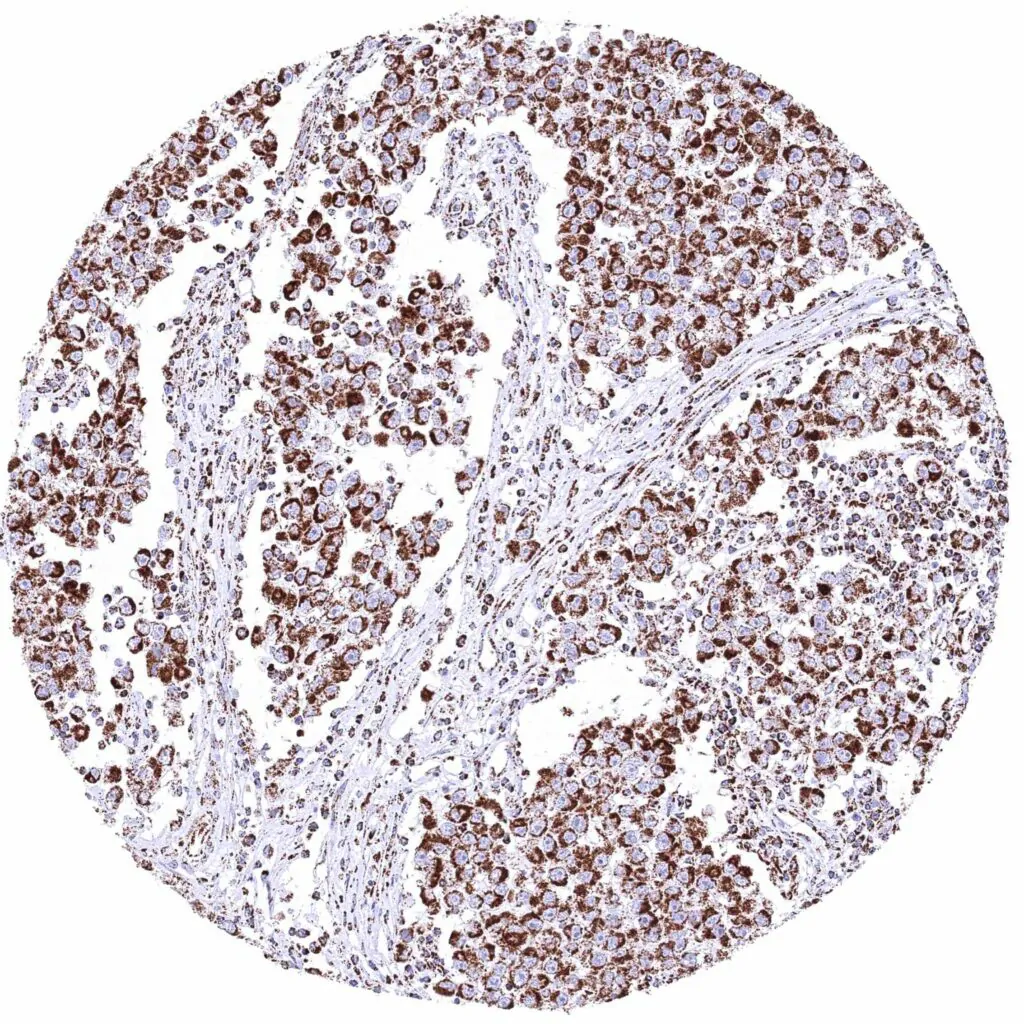

Testis – Seminoma with moderate cytoplasmic ATP5J immunostaining of tumor cells.